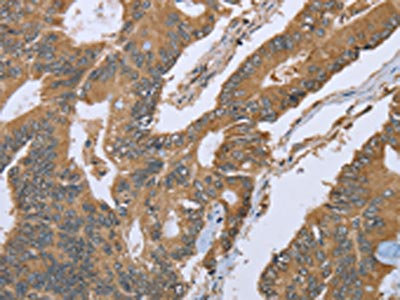

The image on the left is immunohistochemistry of paraffin-embedded Human colon cancer tissue using CSB-PA942640(IL1RN Antibody) at dilution 1/25, on the right is treated with fusion protein. (Original magnification: ×200)

The image on the left is immunohistochemistry of paraffin-embedded Human prostate cancer tissue using CSB-PA942640(IL1RN Antibody) at dilution 1/25, on the right is treated with fusion protein. (Original magnification: ×200)